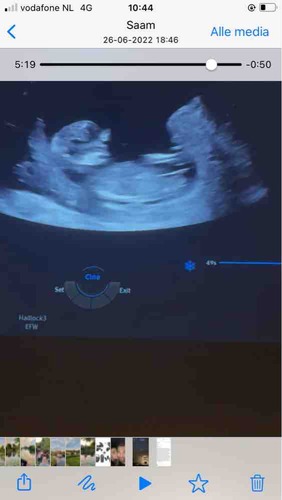

Erg lastig. Vaak verwacht ik wat meer te zien maar lijkt of met de 13 weken echo ze expres de nub wat minder goed op beeld zetten. Op het moment gok ik toch jongen. Door het bolletje erboven en de blaas die lager ligt. Je had niet nog een echo?